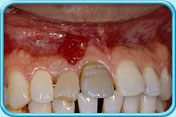

牙齒壞死

因碰撞或蛀牙導致牙齒壞死,壞死的牙髓所釋出的物質滲入象牙質,牙齒就會逐漸呈灰黑色。

這類因牙髓壞死而引致的牙齒變色,必須以根管治療(牙髓治療) 處理。